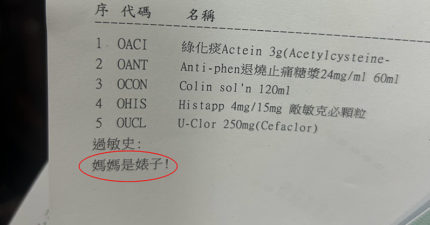

藥單被標註「媽媽是婊X!」人妻看傻 基隆醫院緊急回應了